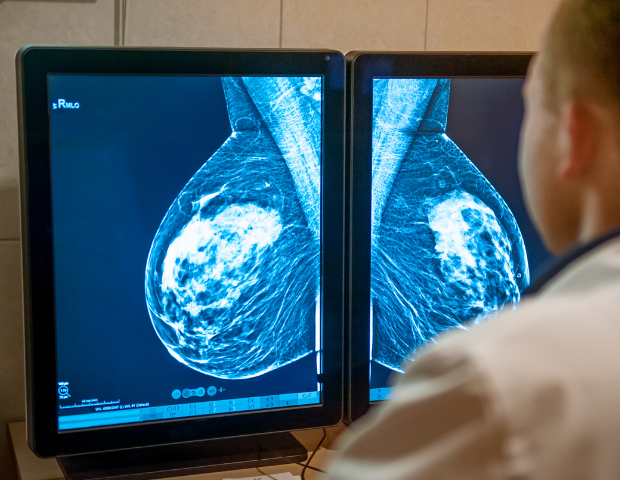

Estudo inédito realizado pela Sociedade Brasileira de Mastologia (SBM) comprova aumento de cerca de 26% nos casos de câncer de mama nos estágios mais graves da doença. O artigo, publicado no International Journal Public Health (IJPH), a partir da análise de dados do DataSUS do Ministério da Saúde, demonstra que a redução do número de mamografias pelo Sistema Único de Saúde (SUS) nos períodos mais críticos da pandemia contribuiu para que novas ocorrências da doença se manifestassem antes do esperado pela comunidade médica. A situação também expõe a necessidade de aprimoramento da saúde pública. “Da forma como o cenário se mostra, o que se espera do Ministério da Saúde são atitudes proativas, com a implementação de um novo modelo de prevenção, diagnóstico e tratamento do câncer”, afirma o mastologista Ruffo Freitas-Junior, assessor especial da SBM.

Em conjunto com Aline Ferreira Bandeira Melo Rocha, Glalber Luiz Rocha Ferreira, Danielle Cristina Netto Rodrigues e Rosemar Macedo Sousa Rahal, Ruffo Freitas-Junior constatou no estudo que o número de mamografias realizadas por mulheres de 50 a 69 anos, faixa etária que constitui a população-alvo para a detecção precoce do câncer de mama, diminuiu significativamente nos períodos críticos da pandemia. Em 2020, foram feitos 1.613.119 exames no serviço público de saúde no Brasil, número 40% inferior às mamografias em 2019 (2.658.289). Em 2021, foram 2.189.734, 18% menor na comparação com 2019, indica o levantamento.

Antes da pandemia, os estadiamentos mais agressivos de câncer de mama representavam 40,8% dos casos. Entre 2020 e 2021, confirma o novo levantamento da SBM, os estágios III e IV são 51,5% dos diagnósticos, de acordo com dados analisados no DataSUS, Departamento de Informática do SUS que monitora o tratamento da doença no Brasil. “A situação, que era ruim, piorou ainda mais. Atualmente, há um avanço de aproximadamente 26% nos estágios III e IV, os mais graves”, afirma.